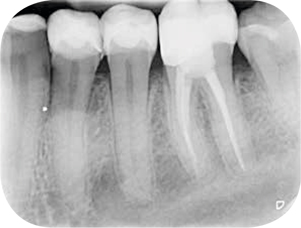

Afb. 9-10

Solo-opnamen van het 1e en 3e kwadrant.

Röntgenonderzoek

Röntgenologisch onderzoek laat meerdere problemen zien. Onder andere een forse zwarting apicaal van element 12 met het beeld passend bij periapicale problematiek en een verleden van apicale chirurgie (afbeelding 8-12 ).